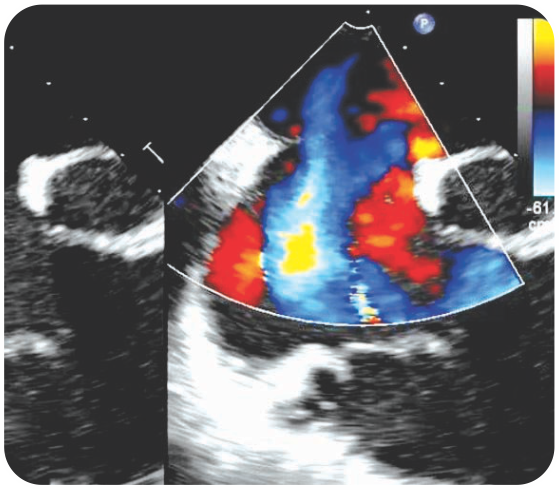

Case 3 - Chordal Rupture - Acute Mitral Regurgitation